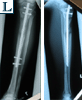

Pre

Op

▪ Bilateral tibial

lengthening

▪ Ilizarov with

lengthening-over-nail

technique

▪ Lengthening at 1mm / day